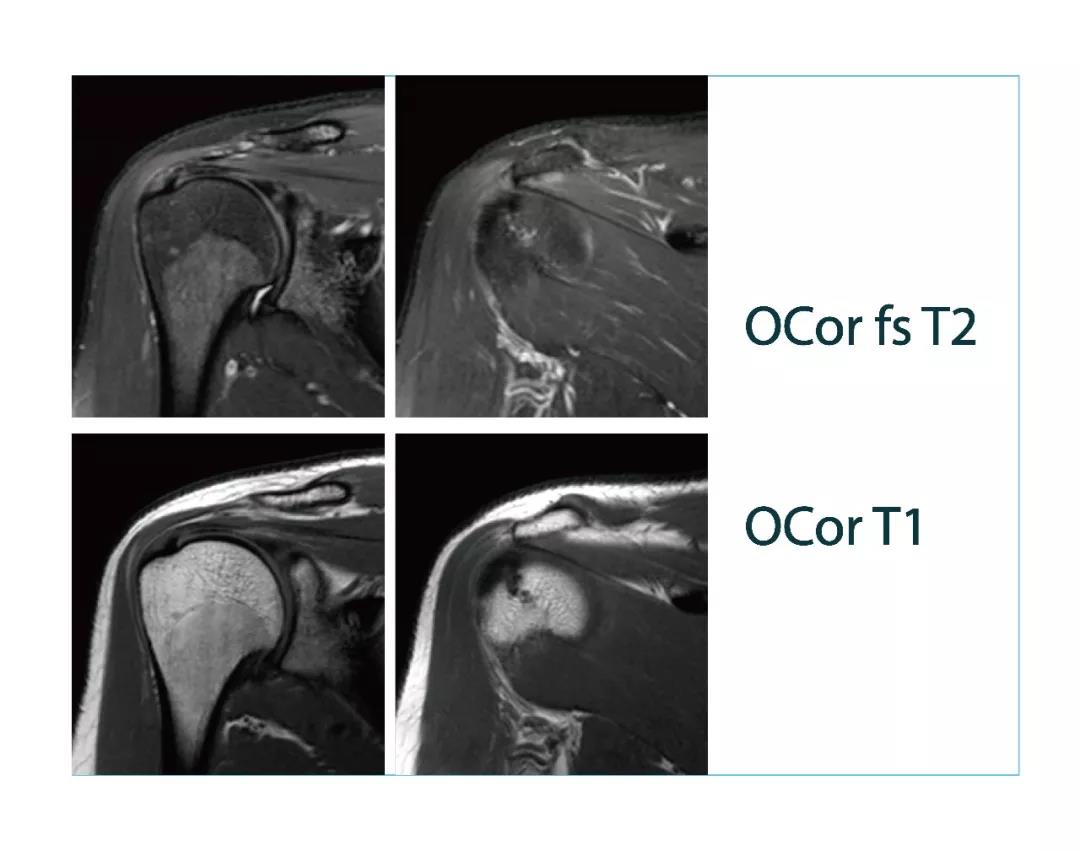

【朗润影像档案】20180330磁共振影像病例结果讨论

【朗润影像档案】磁共振影像病例分享(编号20180330)